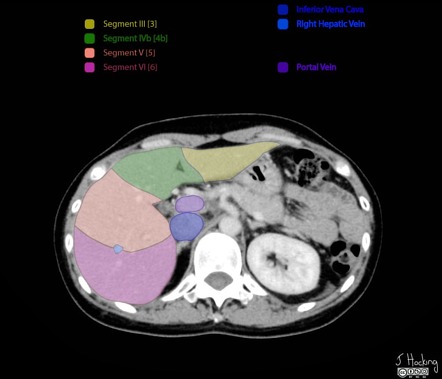

Image | Radiopaedia.org

radiopaedia.org

radiopaedia.org

radiopaedia segments liver ct hepatic radiology anatomy couinaud annotated axial segmentation left classification ultrasound radiological vein vascular nuclear medicine